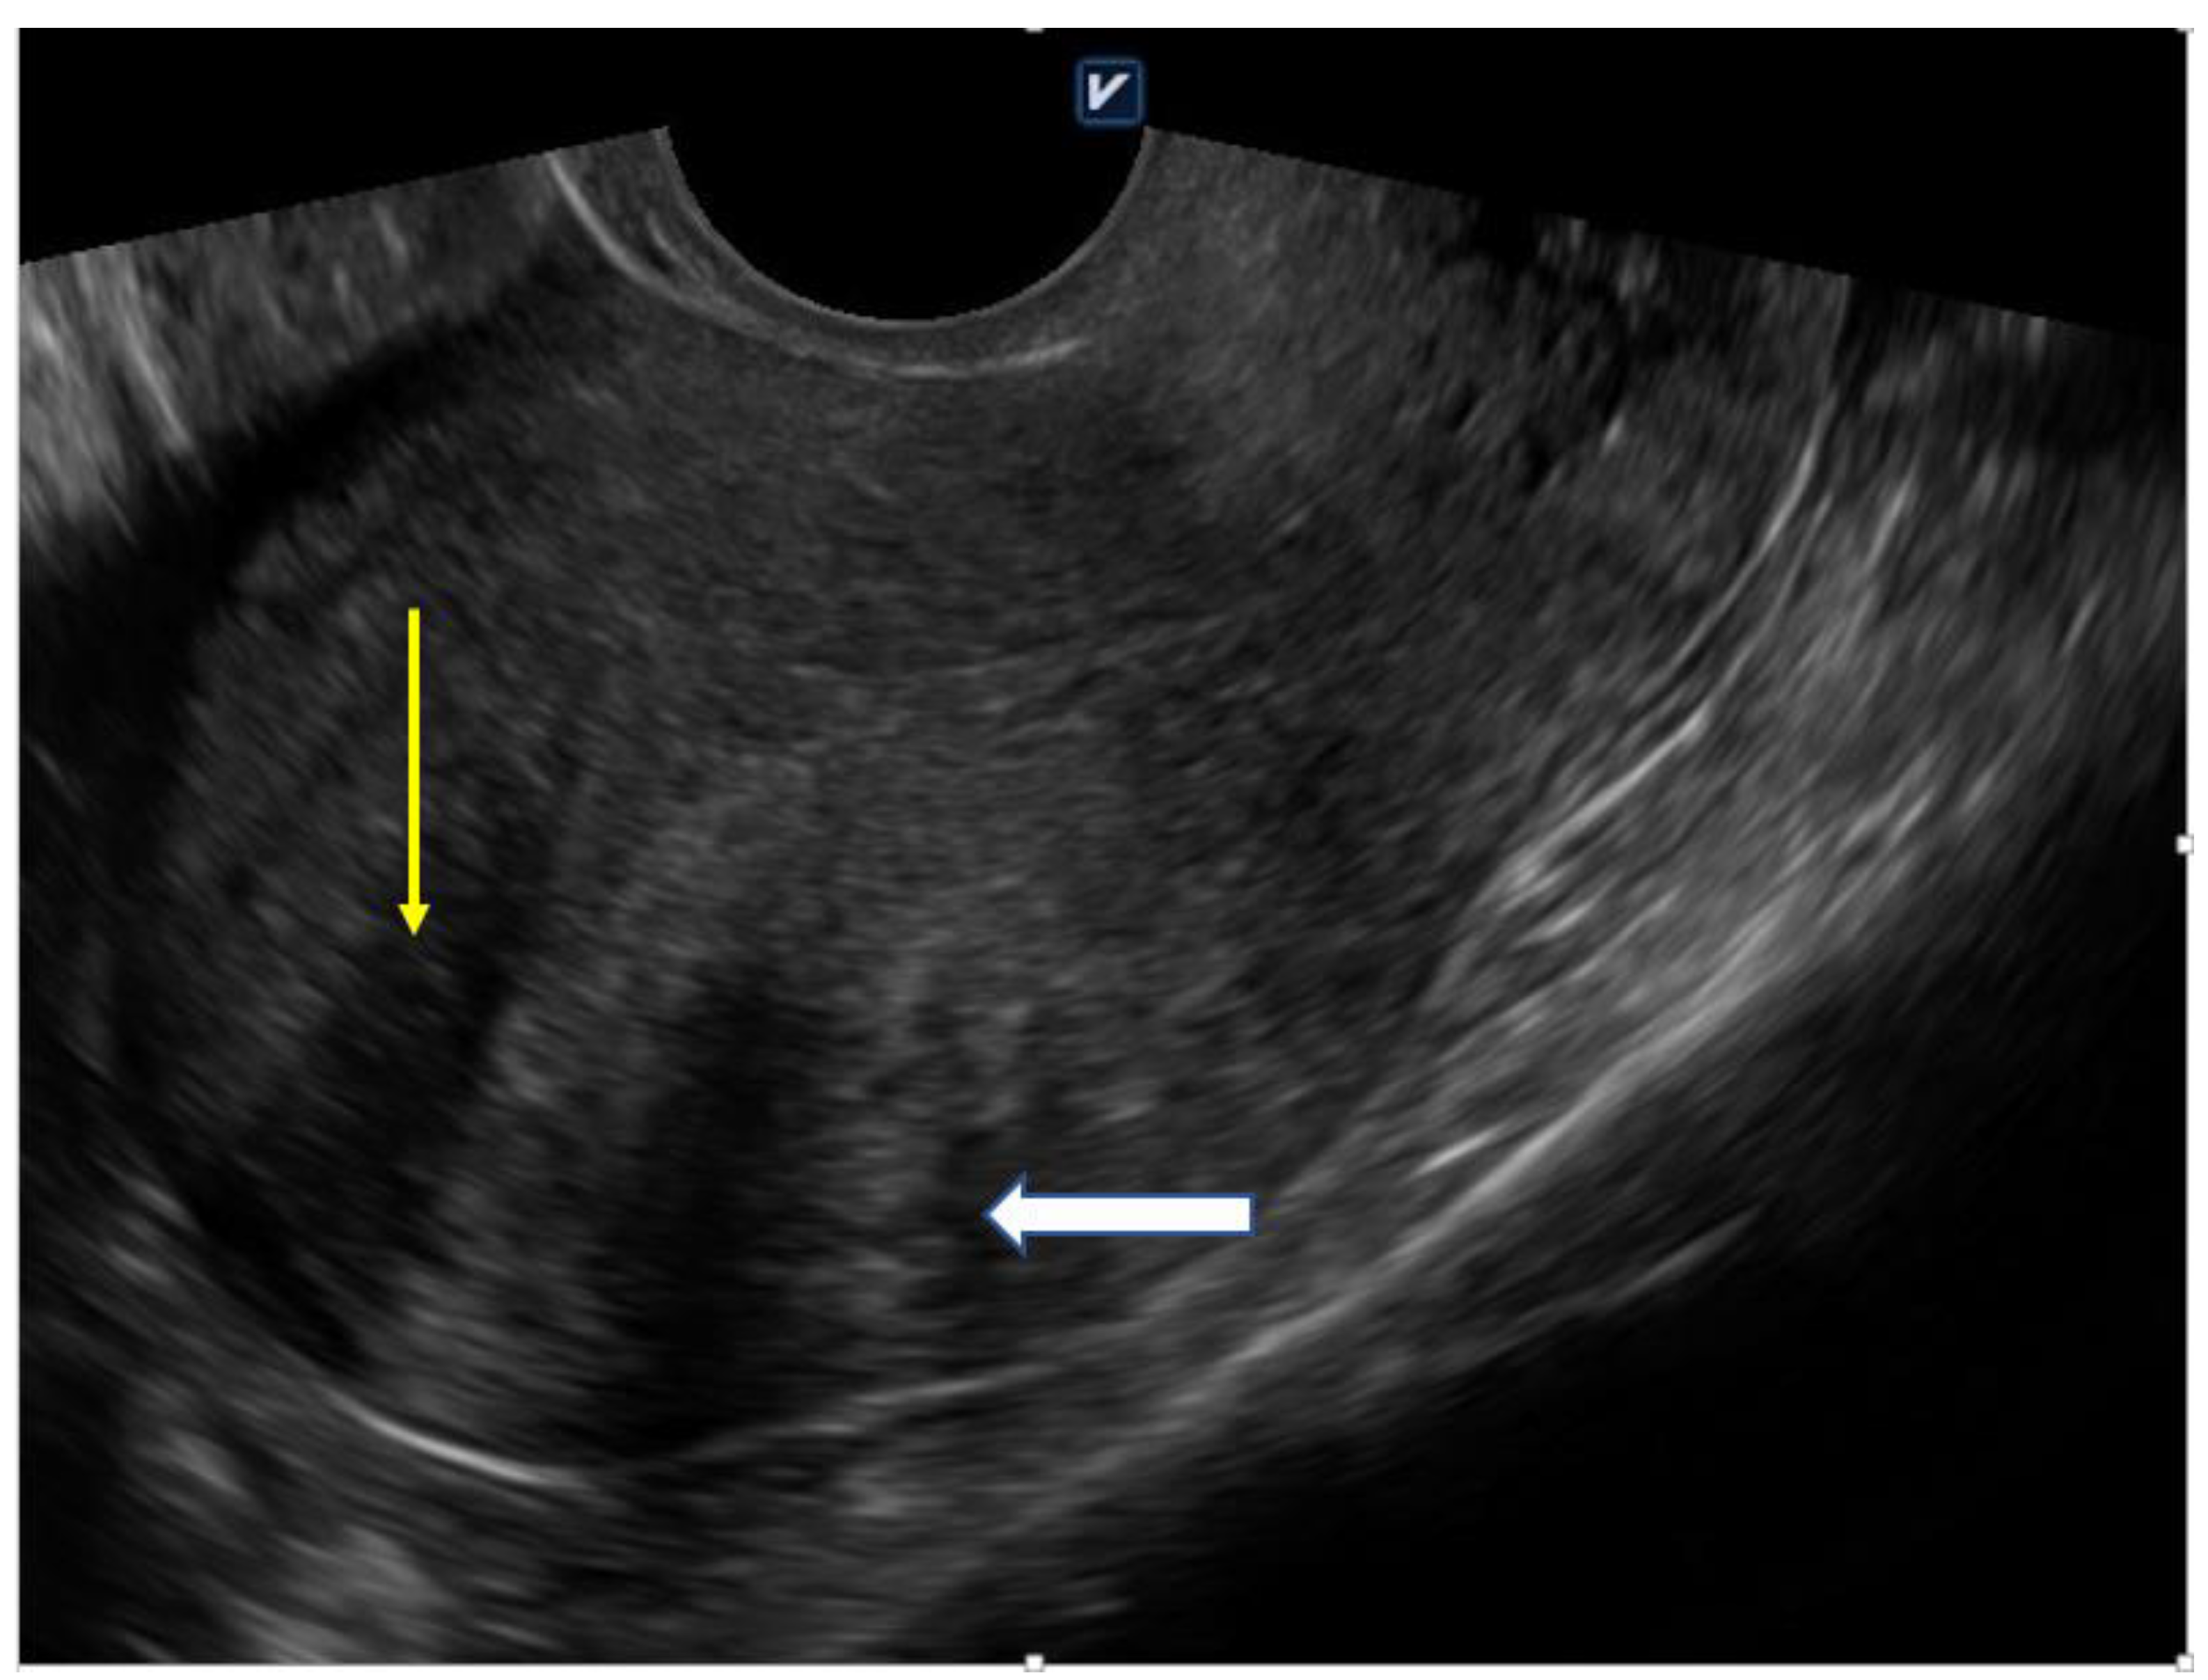

Figure 2.

Globally enlarged uterus with heterogenic myometrium (yellow arrow) and asymmetric thickeness (white arrow); 41 year-old nulliparous woman with 5 years of infertility anamnesis (own material).